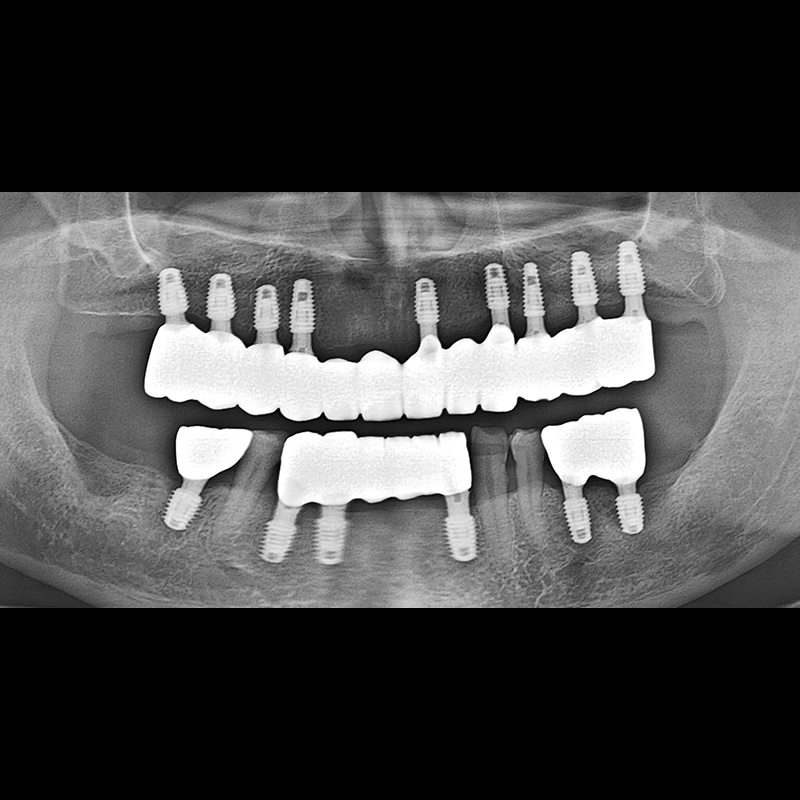

BEFORE AFTER

インプラント手術事例 2025.05.30

欠損した歯の部分と、生かしにくい歯の位置にインプラントを植立しました。